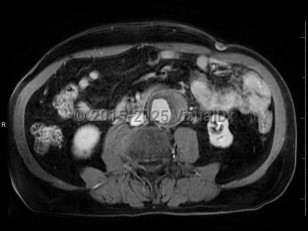

Polycystic kidney diseasePolycystic kidney disease